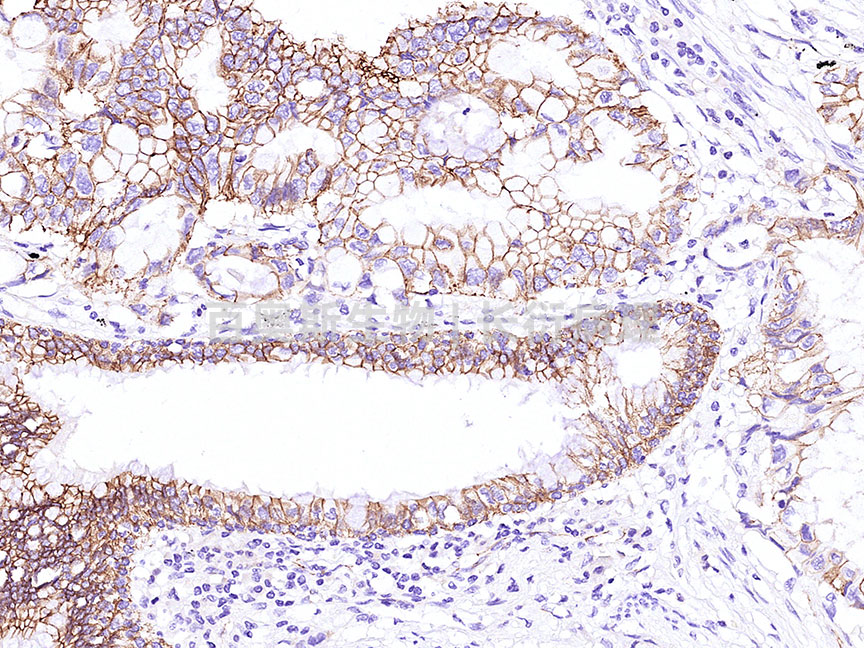

免疫组化单标

项目名称 种属 样本

β-catenin 人 肺腺癌

β-catenin---人-肺腺癌---86底板.jpg